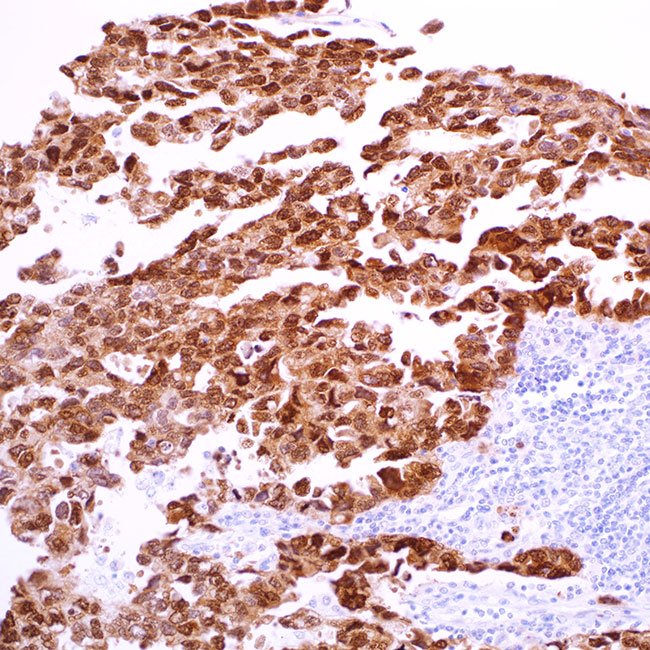

SOX-2 (EP103)

VisualisationNuclear

ControlLung squamous carcinoma (Nuclear)